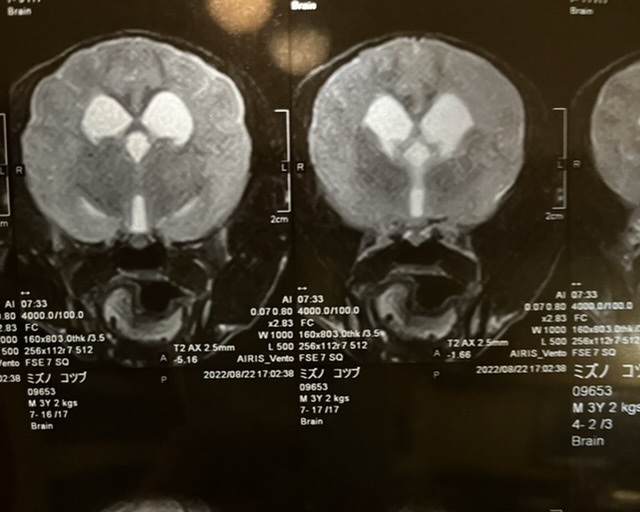

2022年8月22日

MRI検査の結果、脳脊髄炎と診断されました。

同時に脳脊髄液検査をする予定でしたが、脳の腫れがひどく、採取することで脳がずれてしまい亡くなる可能性があるとの事で今回は採取はできませんでした。

脳脊髄液検査をする事で、感染性か非感染性なのかが判明するようですが、こつぶの場合、若くて発症しているので、非感染性で原因不明自己免疫の異常ではないかと言われました。

*病院より掲載のお許しは頂いております